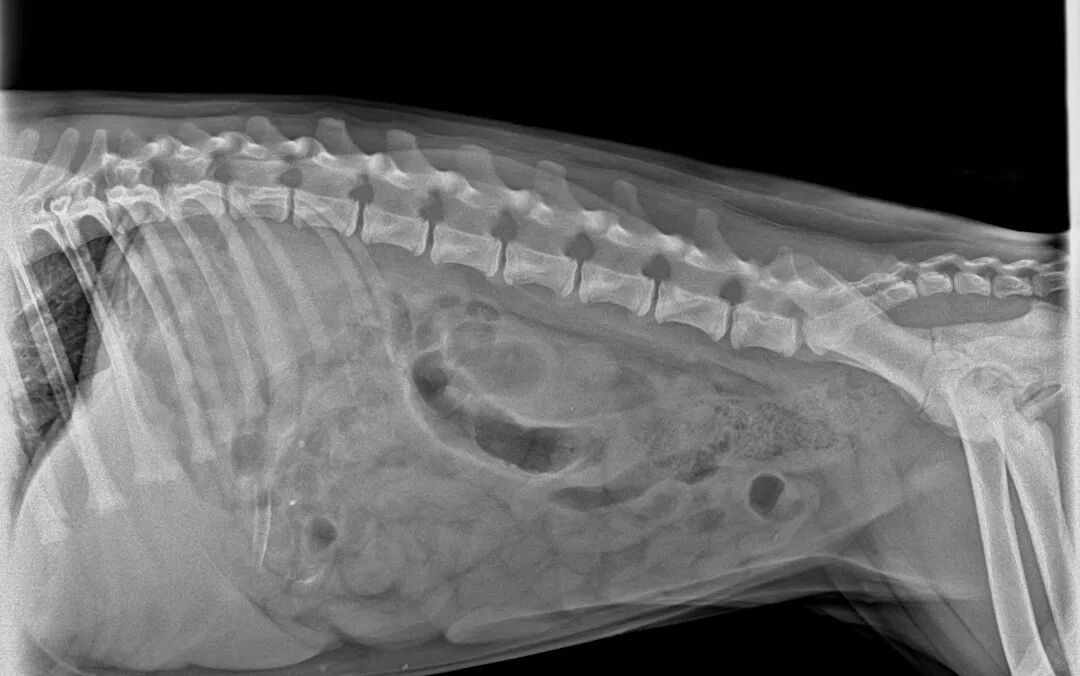

Imagerie DR bloquée sur l'objet étranger

Résultat de l'examen : La radiographie numérique a révélé la présence d'un corps étranger linéaire hyperdense dans l'estomac. L'occlusion intestinale ayant été exclue, le diagnostic retenu est celui de « corps étranger gastrique ».